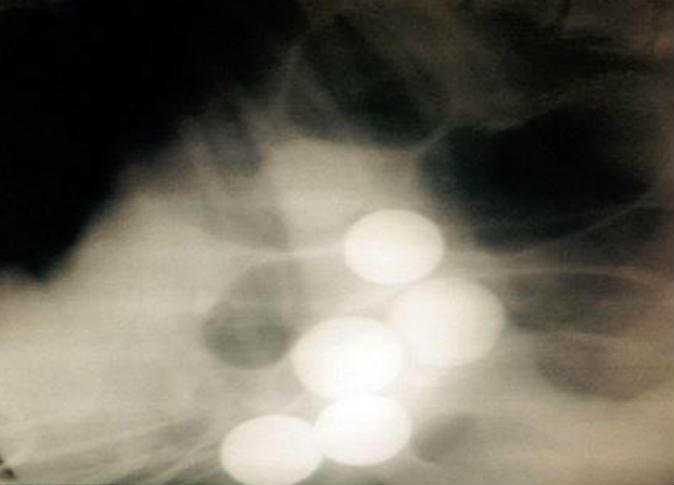

شعر كلب بالتوعك الشديد، أخذه صاحبه ديفيد لارسن إلى مركز العلاج البيطري في مدينة نيوكاسل البريطانية، وسرعان ما نقل الكلب الذي يبلغ من العمر 7 سنوات إلى غرفة العمليات لإجراء عملية عاجلة له، بعد أن أظهرت الصور الشعاعية 6 أجسام كروية في معدته.

وأجرى العملية فريق من الأطباء البيطريين وقاموا بإخراج تلك الأجسام من معدة مورفي حيث اكتشفوا بأن هذه الأجسام ليست إلا كرات جولف.

ويعتقد السيد لارسن الذي أخذ الكلب من مركز رعاية منذ أكثر من عام، بأن الكرات موجودة في معدة الكلب قبل أن يتكفل برعايته لأنه لم يصطحب الكلب إلى أي مكان تتواجد في كرات الجولف على الإطلاق خلال فترة تربيته له.

وأضاف لارسون بأن الكلب "مورفي" شعر بالتوعك بعد أن ابتلع عظمة تسببت في إصابته بالإسهال وآلام شديدة، وأن تأثير كرات الجولف عليه كان كبيراً قبل العملية إذ أنه كان خمولاً وقليل الحركة، ولكنه استعاد نشاطه وحيويته وشهيته بعد استخراج الكرات من معدته.